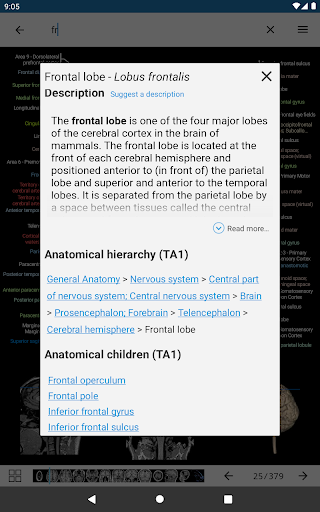

- Ketuk label untuk menampilkan struktur anatomi

*Peningkatan visibilitas definisi bagian anatomi

*Jelajahi bagian-bagian anatomi menggunakan tautan deskripsi

tampilan detail istilah terkait struktur anatomi sekarang ditampilkan